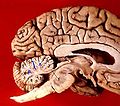

The cerebellum contains similar gray and white matter divisions as the cerebrum. Embedded within the white matter—which is known as the arbor vitae (Tree of Life) in the cerebellum due to its branched, treelike appearance—are four deep cerebellar nuclei. Three gross phylogenetic segments are largely grouped by general function. The three cortical layers contain various cellular types that often create various feedback and feedforward loops. Oxygenated blood is supplied by three arterial branches off the basilar and vertebral arteries.

Gross anatomical divisions

On gross inspection, three lobes can be distinguished in the cerebellum: the flocculonodular lobe, the anterior lobe (rostral to the "primary fissure"), and the posterior lobe (dorsal to the "primary fissure"). The latter two can be further divided in a midline cerebellar vermis and lateral cerebellar hemispheres.